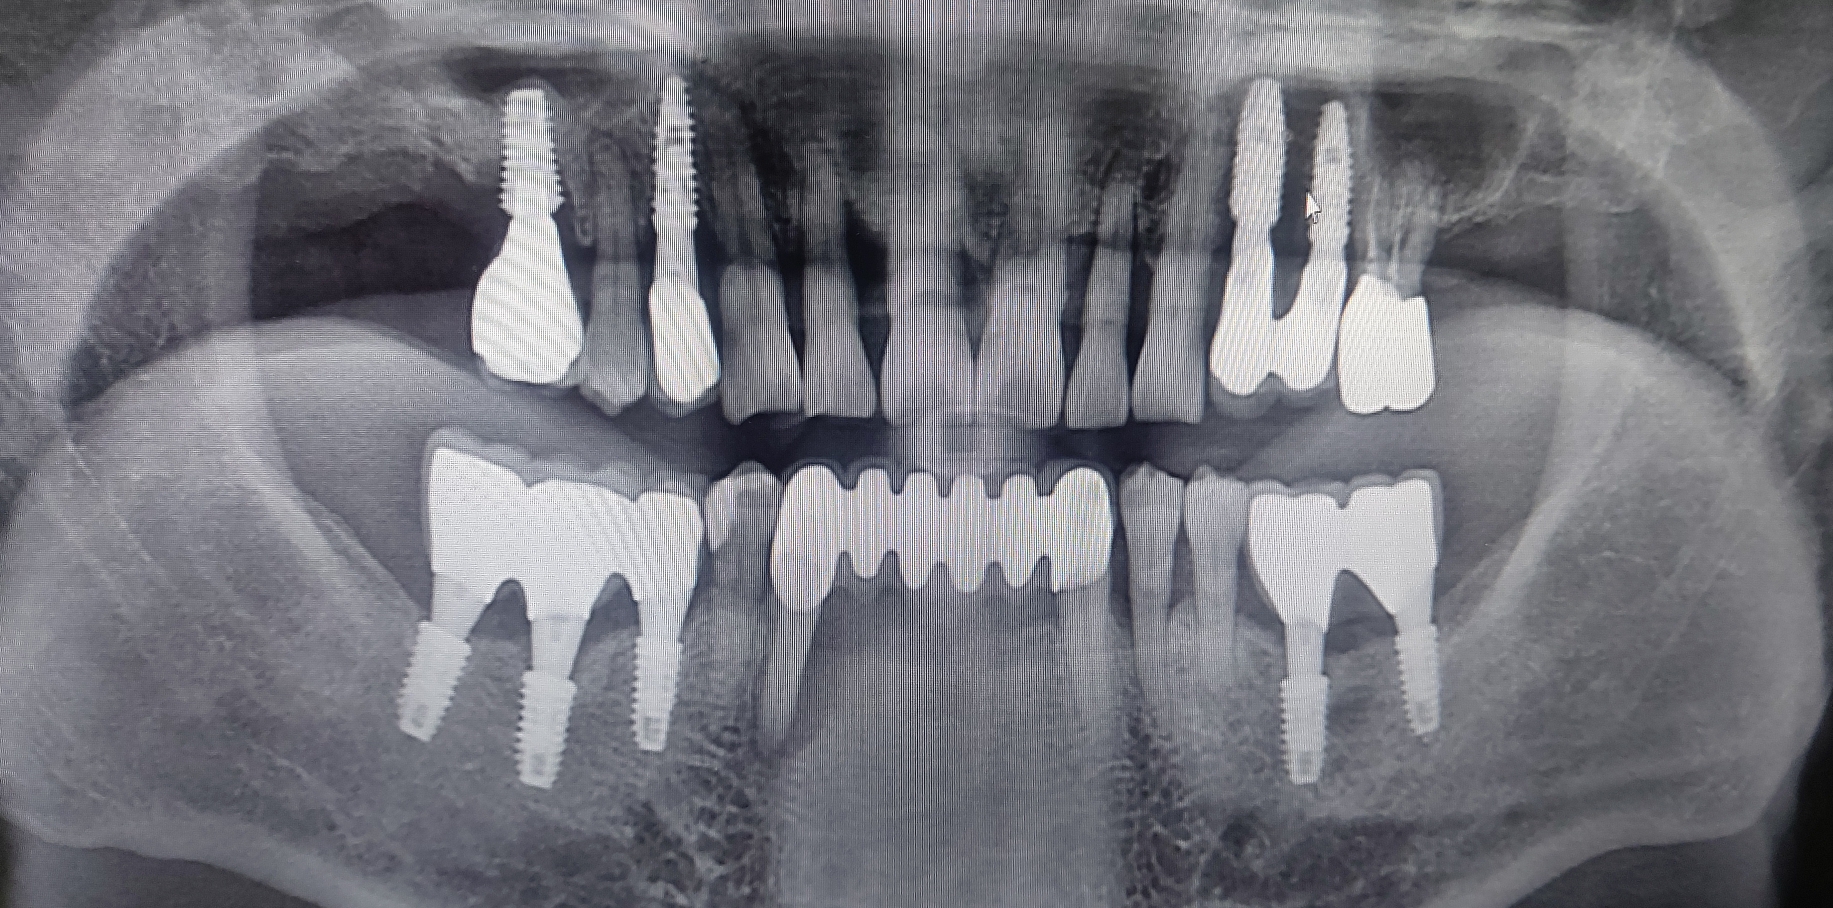

오늘 하악 임시치아의 즉시 부하를 실시한 환자분은 아래 양쪽 송곳니 부위로 연결된 긴 보철물이 있는 환자분이었습니다.

오른쪽 아래 송곳니 부위의 염증이 너무 심하여 잇몸 주위로 많이 부어 있는 상태였고 환자분이 발치 후 보철상담을 하러 오신 경우였습니다.

워낙 젊으신 50대 초반의 남자 환자분으로 앞니 없이 가철성 임시치아로 지내시는 것에 대한 불편감과 여러번 수술에 대한 피로도를 말씀하셔서